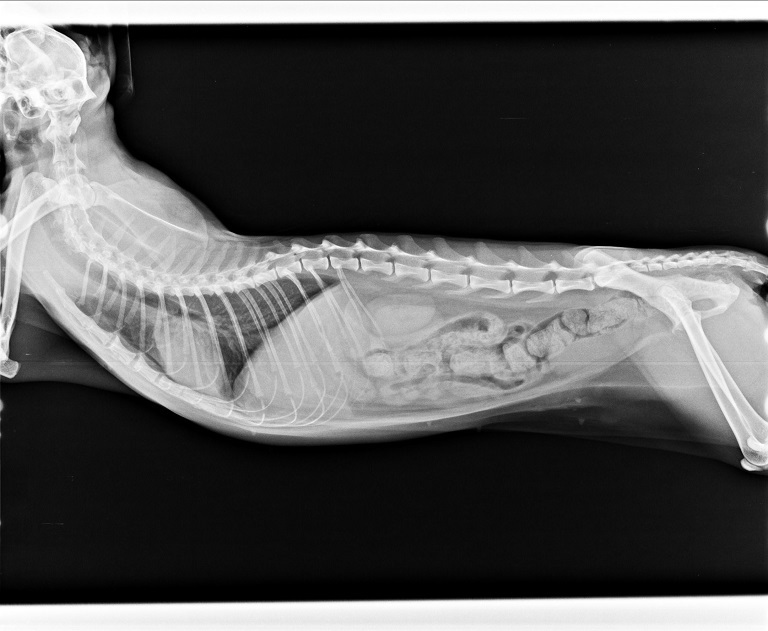

主題: 【住院費】因上呼吸道感染不吃不喝住院的佳音 申請者姓名: 臺北市支持流浪貓絕育計劃協會 花色: 申請日期: 2017-01-02 18:39:38 申請者部落格: 申請者臉書網址: https://www.facebook.com 所在縣市/合作醫院: 台北市/極光動物醫院 治療費用: 42030元 需求人數: 43人 已結案 (2022-05-13 15:17:55) 報名人員: 阿乾(已付款)、林嘉慧(已付款)、Qu Een x2(已付款)、Qu Een x2、Patrick x3(已付款)、Sam、Sam(已付款)、Daniel Tsai(已付款)、Ashley Chang(已付款)、歐提斯(已付款)、熊熊(已付款)、Ironbear(已付款)、王小(已付款)、Yu Hui(已付款)、韓風、paula chen x3(已付款)、林廷軒(已付款)、Double c(已付款)、Daniel Tsai x3(已付款)、Daniel Tsai x3(已付款)、洪凱威(已付款)、youngshiang(已付款)、Carrie Lian(已付款)、阿胖(已付款)、Bella Chen(已付款)、amber(已付款)、Ling Lan(已付款)、Jing Yi Hsu x2(已付款)、陳加諸(已付款)、lavinia x2(已付款)、李 其展(已付款)、ERic YU(已付款)、陳小魚(已付款)、Nina Chiu(已付款)、Cary(已付款)、 候補人員: 動物病情說明: 佳音是北投12貓其中之一,一開始狀況非常的差,不吃不喝,又染上呼吸道病毒送醫,醫生極盡所能的給予協助,在各方面積極治療,做的檢查包含紅白血球檢測、血液生化檢查、耳垢檢查、糞檢、X光片、細菌培養、血型檢測、血巴東核酸診斷檢驗、貓瘟病毒篩檢,針對佳音的狀況給予皮下點滴注射、口服第一、二線抗生素、口服化痰藥、口服抗組織胺、食慾促進劑、腸內寄生蟲驅蟲藥、口服消化酵素、耳藥水、靜脈止吐針劑、胃乳、肌肉注射鐵劑、益補血、噴霧、食道胃管灌食等等,在醫師團隊的努力下,經歷了23的治療,佳音身體逐漸好轉,已經出院在安養之家調養身體。